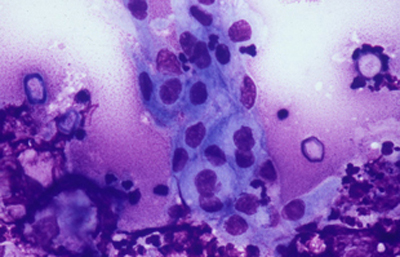

Tanto las Acanthamoebas vivas como sus productos de degradación son marcadamente antigénicos. En la respuesta celular a la infección por Acanthamoeba, los macrófagos las fagocitan (Fig 19) y los neutrófilos las destruyen vía secreción de mieloperoxidasas. (Figura 20) (Para no frenar la respuesta celular, preferimos no usar corticoides en el tratamiento de la infección activa). (El uso crónico de corticoides, en casos con superficie corneal alterada, es un factor primario en el desarrollo de una queratopatía cristalina infecciosa). La respuesta celular tiene como consecuencia, cuando la invasión por Acanthamoebas es estromal, que la abscesificación del estroma continuará aumentando a pesar del tratamiento, siendo su resolución lenta. (Figura 21, 22, 23, 24, 25, 26) (Figura, 27, 28, 29 y 30)

Fig. 19 Acanthamoeba fagocitada por macrófago. Giemsa, Original x160

Fig. 20 Trofozoito rodeado por polimorfonucleares. Giemsa, Original x160